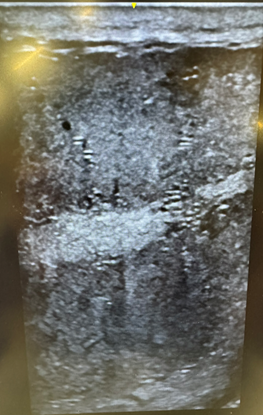

kAm%6DE:4F=2C 5686?6C2E:@? DE2CED 2E E96 >:4C@D4@A:4 =6G6=]k^Am

kAm$A6C> 2C6 AC@5F465 :? 2 =@?8[ 4@:=65 EF36 :?D:56 E96 E6DE6D 42==65 E96 D6>:?:76C@FD EF3F=6] (96? E9:D DECF4EFC6 DE2CED E@ 5:D:?E68C2E6[ E96C6 :D 2 D:8?:7:42?E C65F4E:@? :? DA6C> 4@?46?EC2E:@? 2?5 D4C@E2= 4:C4F>76C6?46] (:E9 E92E E96C6 :D 2? :?4C62D6 :? :?4@CC64E=J D92A65 DA6C> 46==D]k^Am

kAm|@DE @7 E96 E:>6[ 3@E9 E6DE:4=6D 2C6 27764E65] %96D6 492?86D 42? =625 E@ DF376CE:=:EJ 2?5 6G6? A6C>2?6?E :?76CE:=:EJ]k^Am